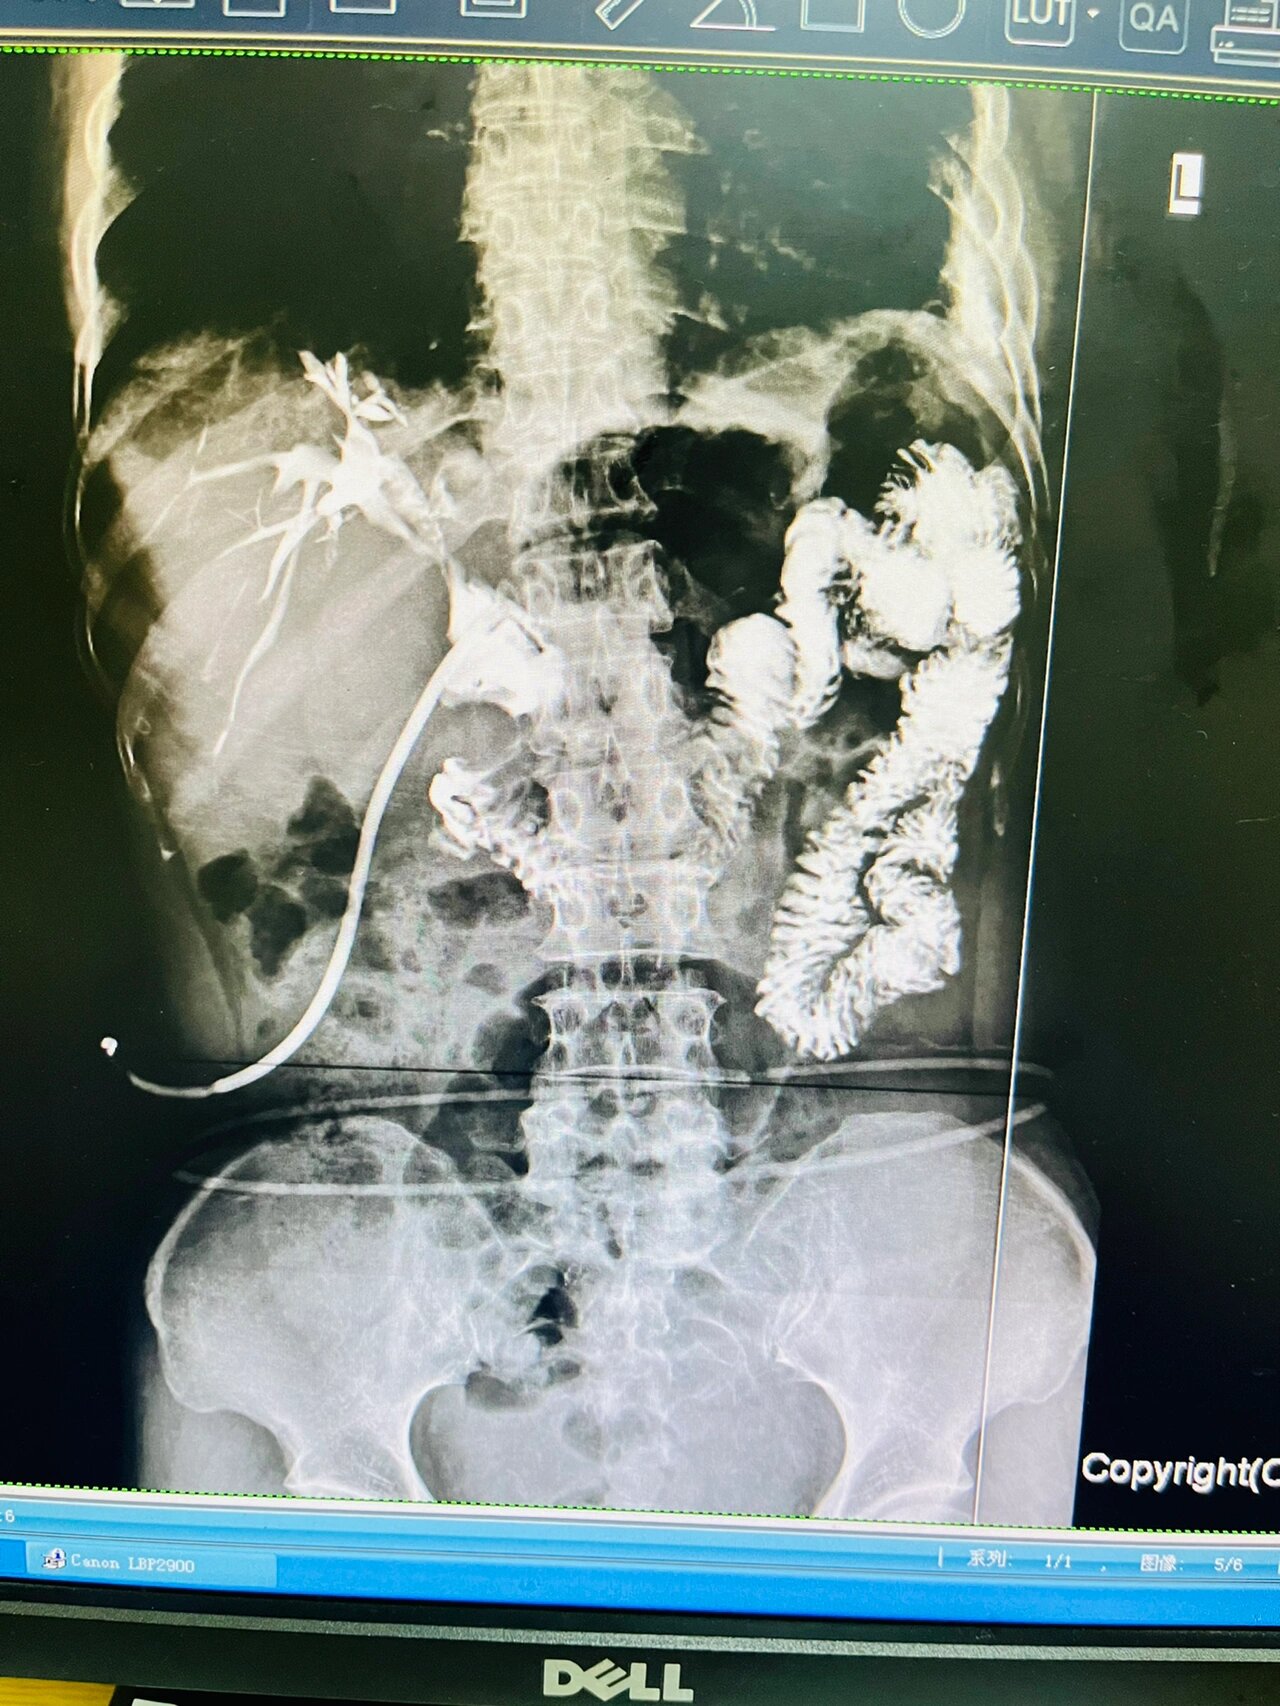

术中抽出的部分血栓▲ 冲洗后的胆道造影图像▲ 造影提示胆管内

术后t管造影 未见明显结石残留